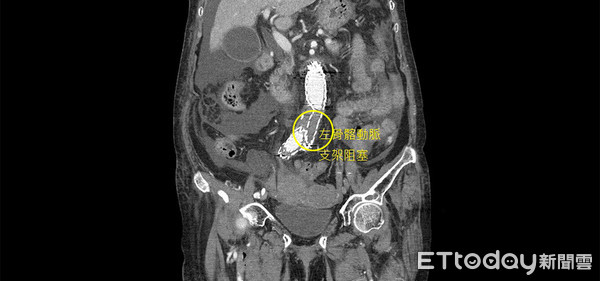

透過電腦斷層發現,患者8年所放置的腹主動脈支架,因未做定期追蹤,造成左骨髂動脈支架嚴重阻塞,而右骨髂動脈支架末端有8公分大的血管瘤,隨時有破裂的危險。

▲左骨髂動脈支架嚴重阻塞。